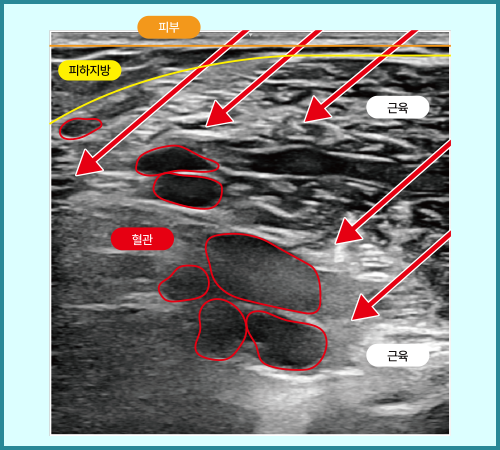

초음파 정밀분석으로 근육의 깊이·형태·혈관 분포를 실시간으로 파악하며,

근육의 깊이·형태·혈관 분포를 초음파로 정밀하게 육안으로 확인하고,

초음파로 근육, 혈관 실시간 모니터링

근육과 혈관 구조를 실시간으로 확인, 안전하고 정확한 시술 설계